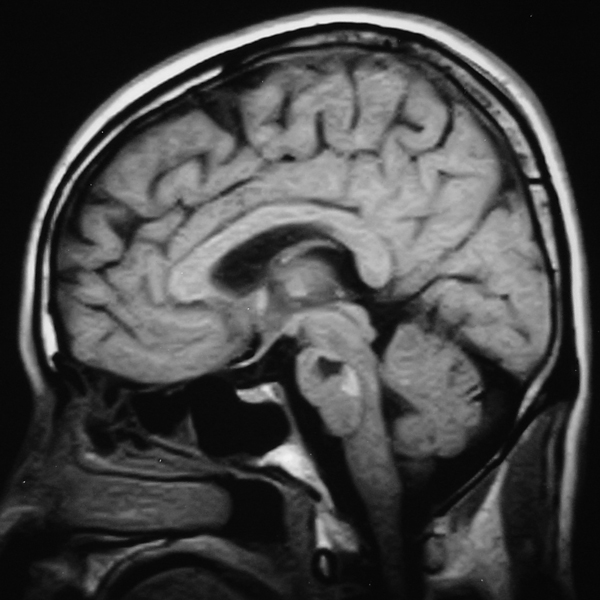

脑位于颅腔内,可分为脑干、小脑、间脑、端脑。

脑干属于脑的一部分。

(一) 脑干分部

脑干包括延髓、脑桥、中脑三部。

(二) 脑干位置

位于颅后窝,自枕骨大孔至蝶鞍之间。

(三)脑干外形

下端较细,与脊髓表面沟裂相续,中上部较宽大。

1.腹面观

(1)延髓:主要结构有锥体和锥体交叉。

(2)脑桥:借延髓脑桥沟与延髓分界。主要结构有基底沟等。

(3)中脑:主要结构有两个大脑脚和脚间窝等。

2. 背面观

(1)延髓:主要结构有薄束结节、楔束结节。

(2)脑桥:脑桥和延髓之间是菱形窝。菱形窝两侧有与小脑相连的小脑脚。

(3)中脑:有四叠体,即两个上丘和两个下丘。上丘与视觉反射有关,下丘与听觉反射有关。